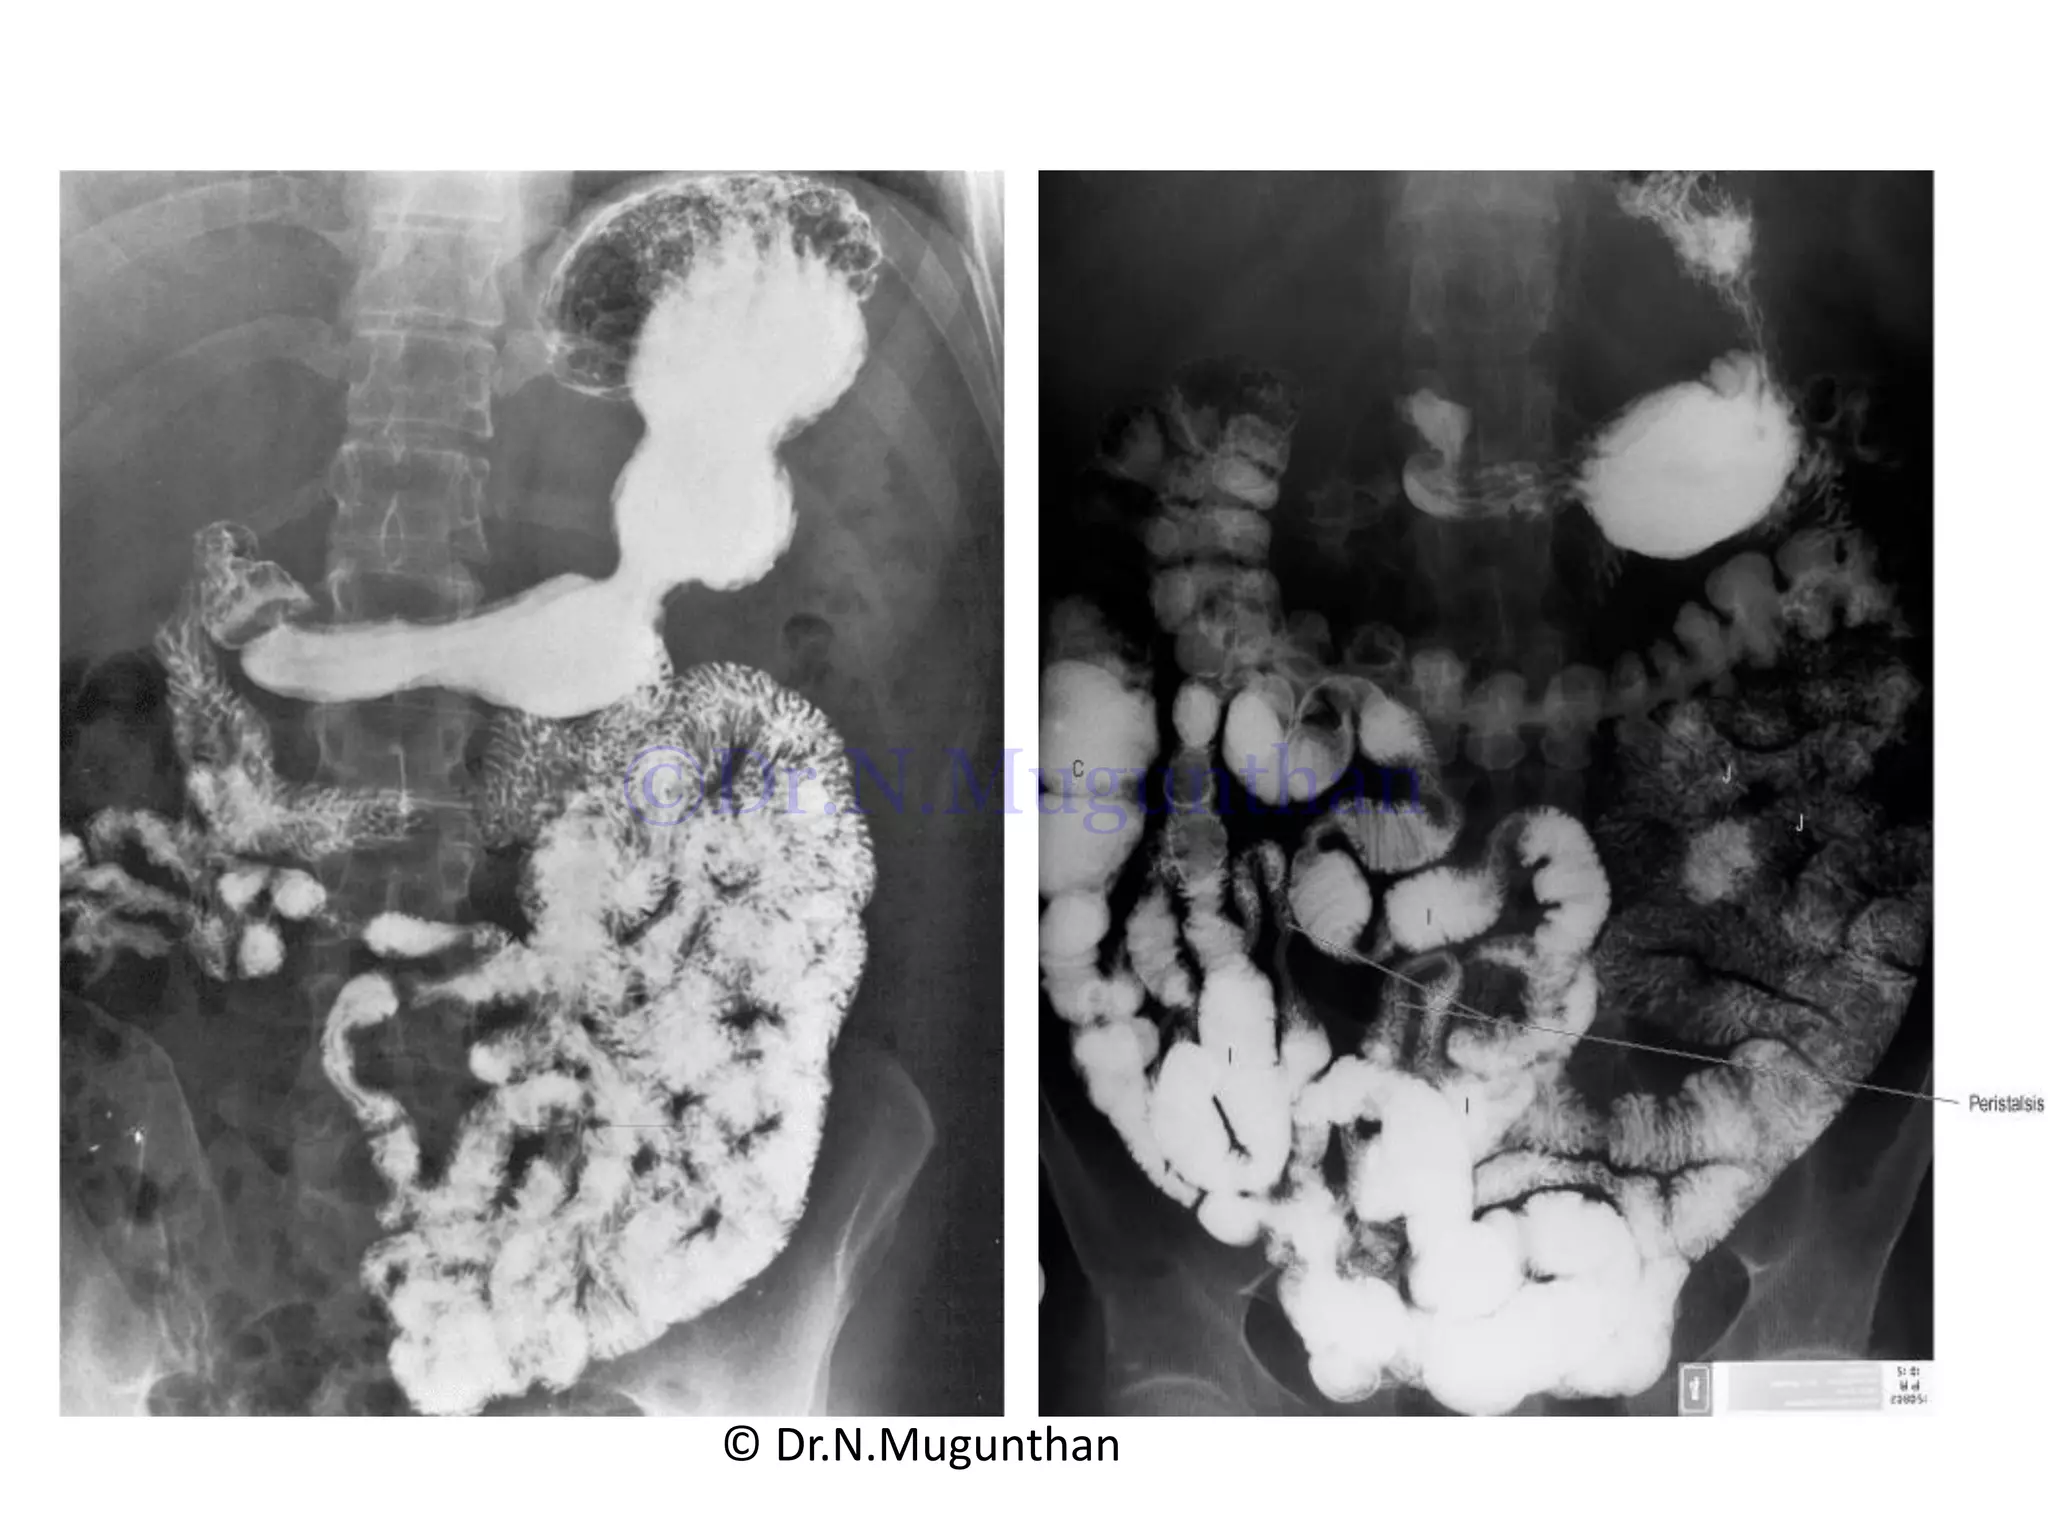

Jejunal branches Ileal branches

Few arterial arcades & long vasa recta More arterial arcades & short vasa recta

DIFFERENCES BETWEEN JEJUNUM& ILEUM S.No Jejunum Ileum 1. Location Upper part of the peritoneal cavity Lower part of the peritoneal cavity 2. General appearance Wider , thicker walled and reddish Narrower, thin walled and paler 3. Attachment of mesentery To the posterior abdominal wall above and to the left of the aorta Below and to the right of the aorta. 4. Arterial arcades Only one or two arcades / vasa recta is long Three or four or even more arcades/vasa recta is short 5. Translucent windows Translucent windows are clearly seen (less fat) Translucent windows are not clearly seen (more fat) 6. Interior a. Plicae circularis – larger & more numerous b. Villi-longer and more numerous. c. Payer’s patches -absent A.Plicae circularis – smaller & less numerous B. Shorter and less numerous C. Payer’s patches -present© Dr.N.Mugunthan ©Dr.N.Mugunthan

Jejunal branches Ilealbranches Few arterial arcades & long vasa recta More arterial arcades & short vasa recta © Dr.N.Mugunthan ©Dr.N.Mugunthan